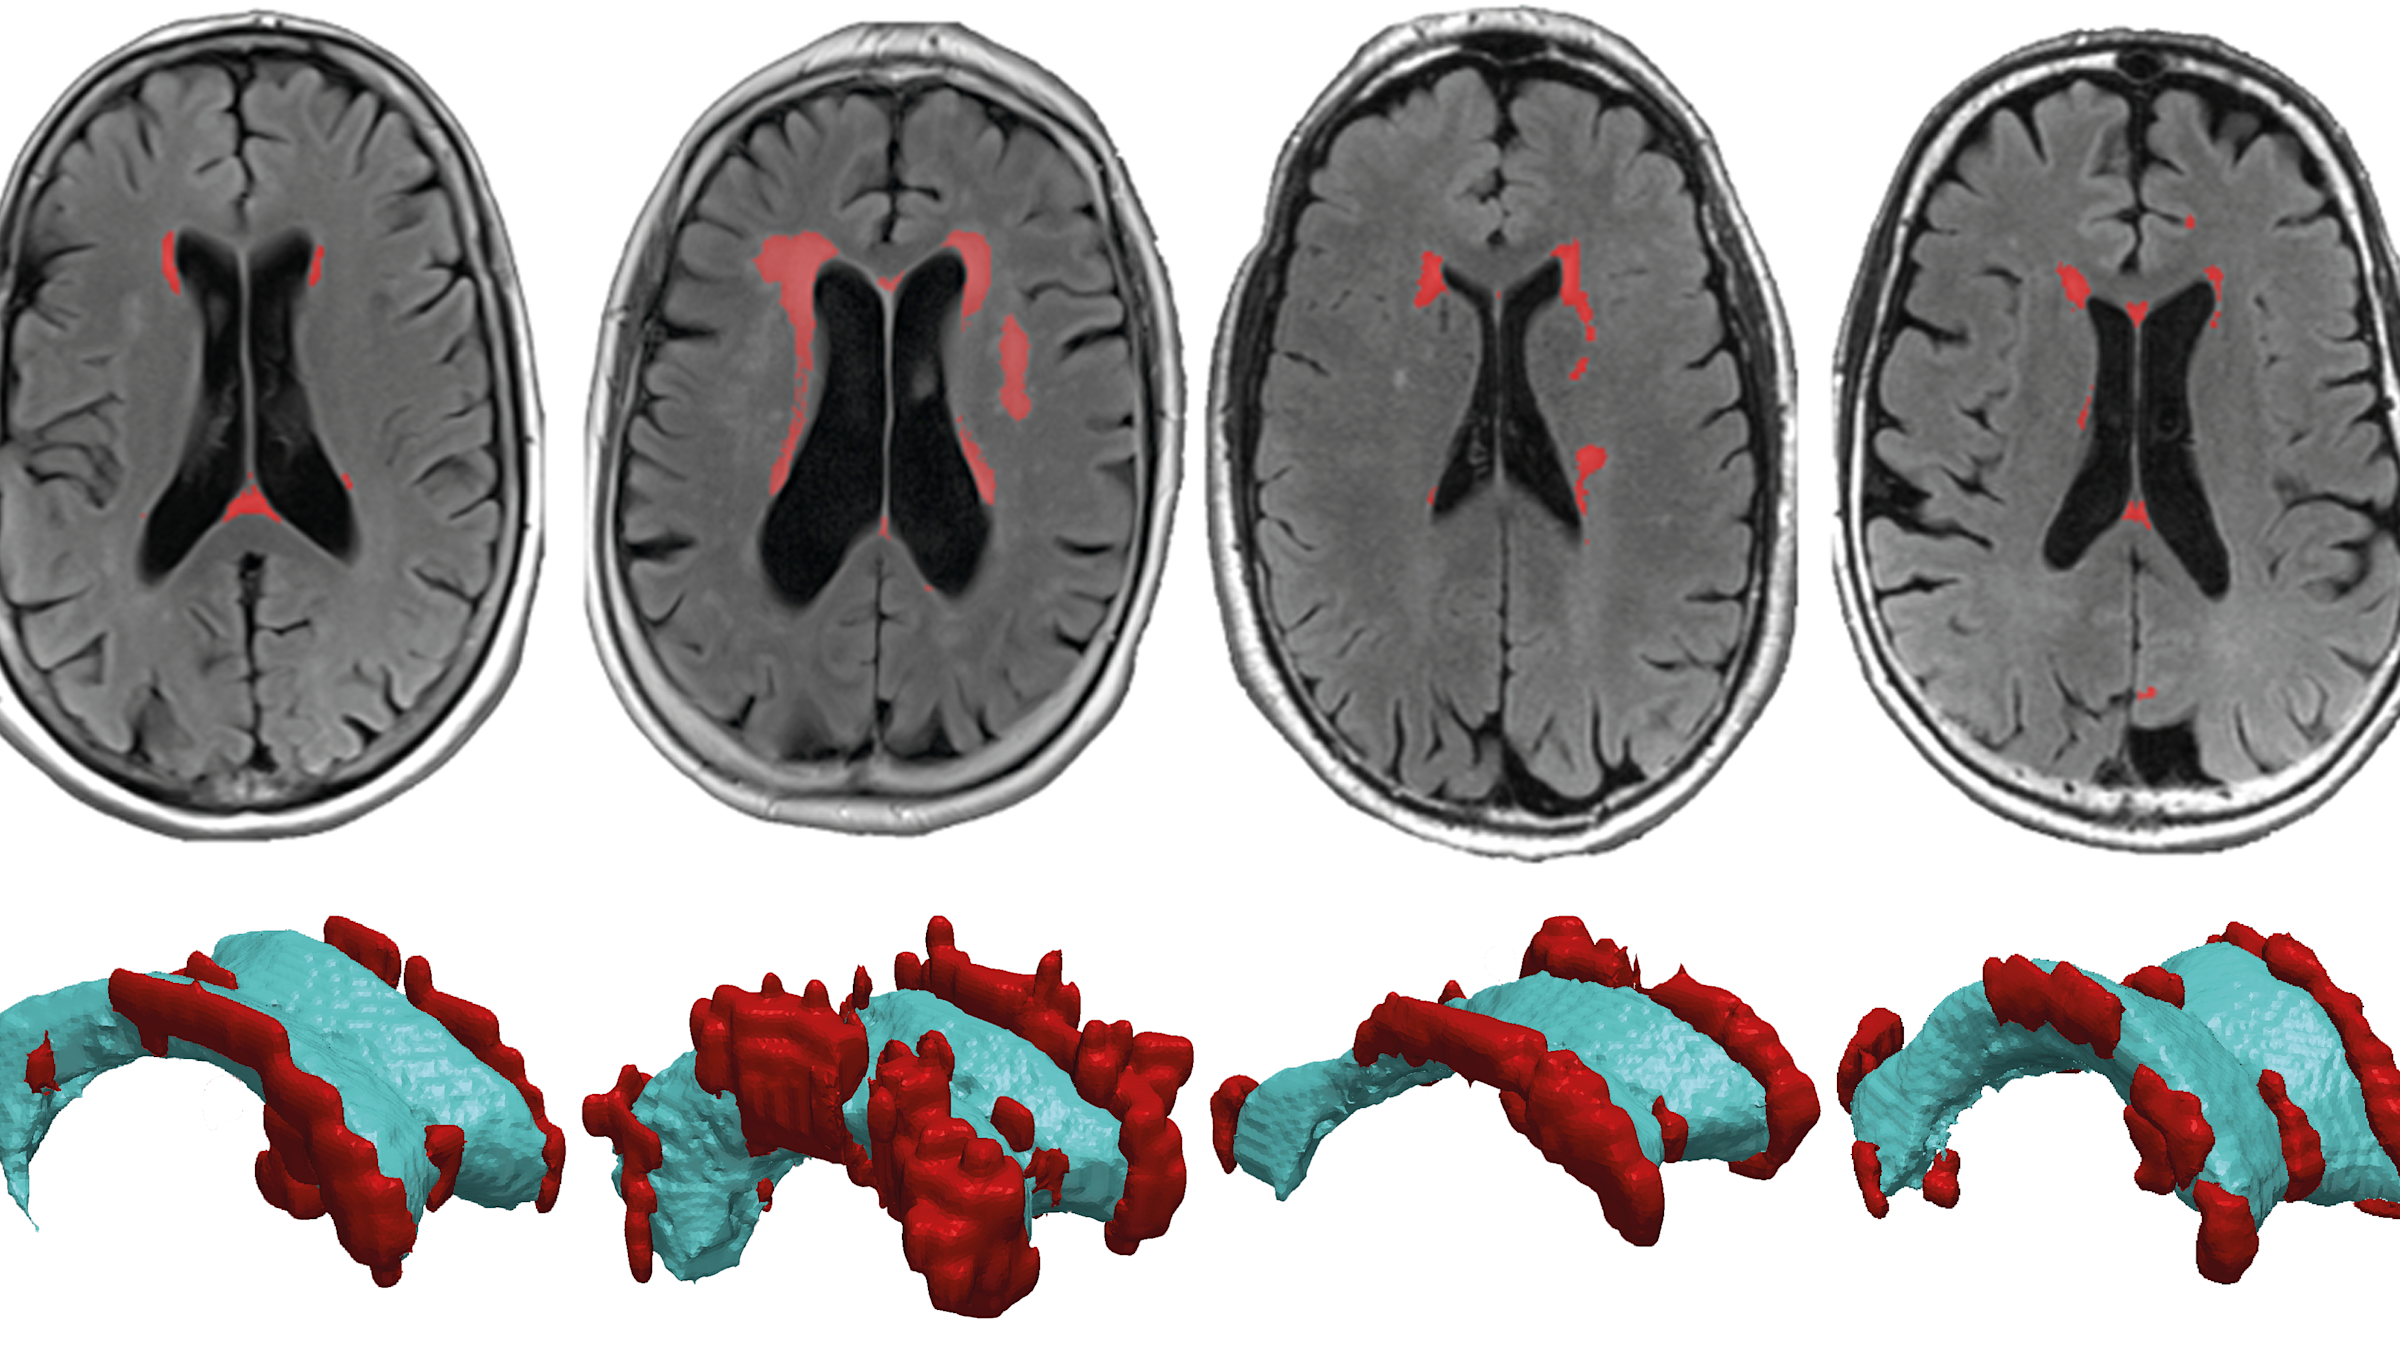

These lesions — known as deep and periventricular white matter hyperintensities because they show up as bright white patches on MRI scans — are poorly understood. But they are not uncommon: most people have some by the time they reach their 60s, and changes only increase with age. The more lesions that accumulate and the faster they grow, the more prone we become to cognitive impairments ranging from memory problems to motor disorders.

Using MRI scans from eight healthy subjects, Weickenmeier worked with Valery Visser, now a doctorate student at the University of Zurich, and Henry Rusinek, a radiologist at NYU Grossman School of Medicine, to develop an individualized computer model of each subject’s brain. The team mapped the strain placed on ventricular walls, the linings of fluid-filled chambers deep in the brain, as waves of pressure pulse through the subject’s cerebral spinal fluid, or CSF. They found that hyperintensities tend to occur near areas that must stretch more to accommodate pressure changes of the circulating CSF because, as such areas wear thin, CSF can leak into the brain and cause lesions.

“The cell wall that lines the ventricles wears out over time, like a balloon that’s repeatedly blown up and deflated,” said Weickenmeier. “And the stresses aren’t uniform — they’re defined by the geometry of the ventricle, so we can predict where these failures will occur.”